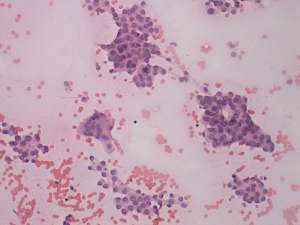

Cytology. Papillary cancer was diagnosed in the nodule in the left lobe and a metastasis of the thyroid cancer into one of the enlarged lymph nodes.

Histopathology. Papillary cancer in the left lobe with metastasis to the lymph nodes, and hyperplastic nodules in the right lobe.